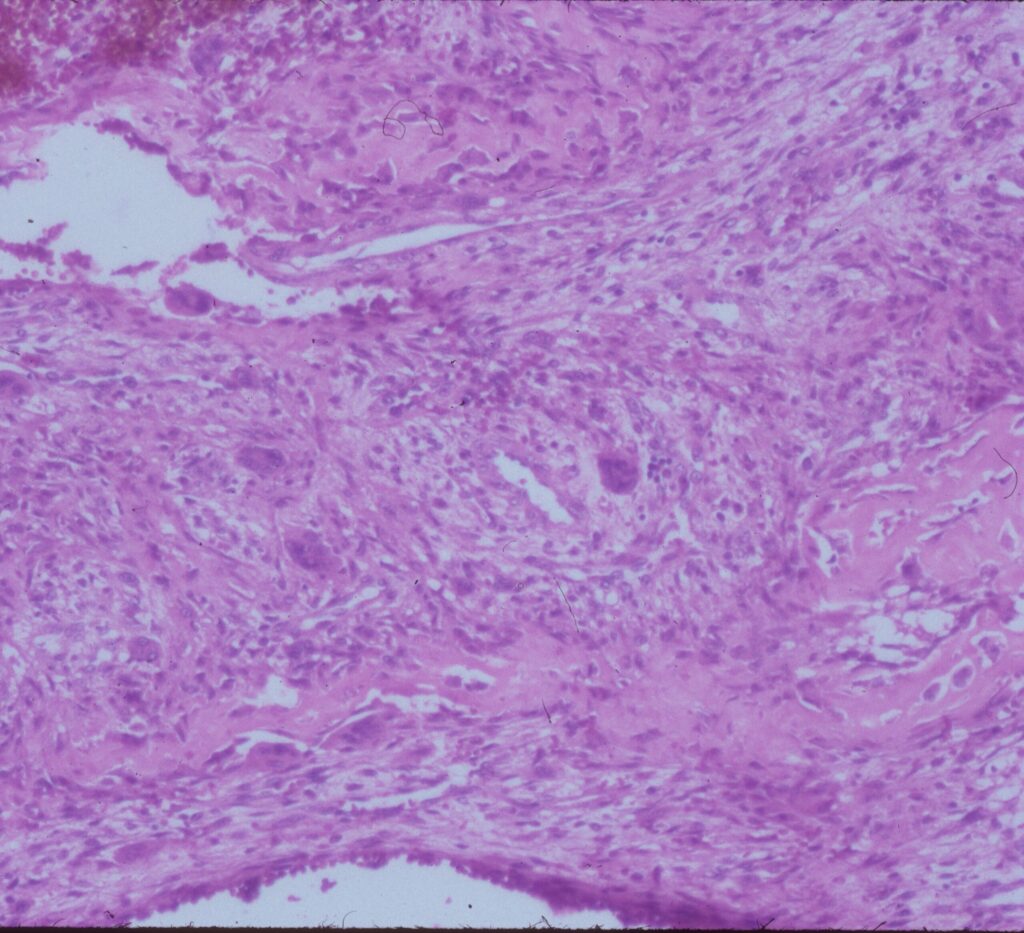

Microscopic Pathology

- Hemorrhagic tissue with large cavitary spaces divided by septum of spindle fibroblastic cells, inflammatory cells and few giant cells.

- Osteoid formation could be noted (reactive and benign in nature)

Fig 3 a,b,c. Microscopic pathology of an Aneurysmal Bone Cyst (ABC):

Figure 3a: There is a large blood filled cystic cavity surrounded by a fibrous septae that includes benign appearing spindle cells, fibrous extracellular matrix and scattered giant cells. There are areas of reactive bone formation. The fibroblastic cells are bland appearing. There are no abnormal mitotic figures.

Fig 3b: Intermediate power of a septum of an ABC: There is no epithelial lining around the wall of the cavity filled with blood. There are spindle cells and scattered giant cells.

Fig 3c: High power view of an ABC: Demonstrates reactive bone formation within the wall of the cystic cavities. This is reactive bone and different from the lace like immature bone layed down by an osteosarcoma